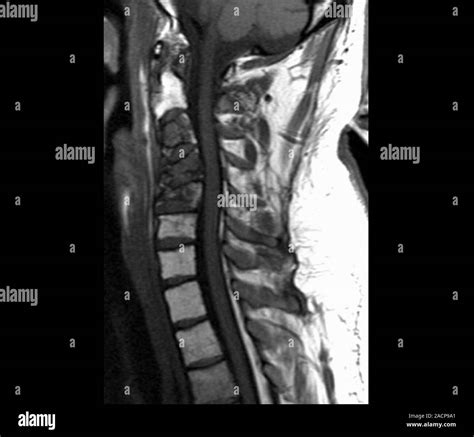

When you experience persistent neck pain, radiating discomfort into your arms, or unexplained numbness, your physician may recommend an MRI of the cervical spine. This advanced diagnostic imaging tool is the gold standard for visualizing the delicate structures of your neck, including the spinal cord, nerve roots, and the vertebrae themselves. Unlike X-rays, which primarily show bones, an MRI uses powerful magnetic fields and radio waves to create detailed, cross-sectional images of both hard and soft tissues. Understanding what this procedure entails can help alleviate anxiety and ensure you are prepared for your appointment.

The cervical spine comprises the top seven vertebrae of your spinal column, labeled C1 through C7. This area is highly complex and functionally vital, as it protects the spinal cord and allows for a wide range of head and neck movement. An MRI of the cervical spine provides a comprehensive view of several critical components:

The images produced by an MRI of the cervical spine are reviewed by a radiologist—a physician specialized in interpreting medical imaging. The radiologist will look for patterns, signal abnormalities, and structural changes that correlate with your clinical symptoms. The findings are compiled into a report sent directly to your referring physician, who will then discuss the results with you in the context of your overall health and physical examination.

The primary advantage of using an MRI of the cervical spine over other imaging modalities is its superior soft-tissue contrast. Because the spinal cord and nerve roots are essentially soft tissue structures, standard X-rays are largely ineffective at visualizing them. By utilizing contrast agents in some cases, radiologists can also identify inflammation or vascular issues that are not visible on plain films. Furthermore, MRI involves zero ionizing radiation, making it a safer long-term option compared to repeated CT scans or X-rays.